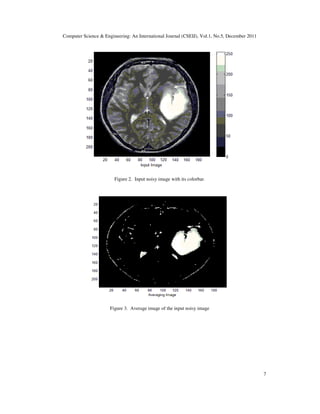

Firstly, we use a brain MRI image an abnormal condition is presence. In this MRI image, there is

a tumer. In Fig (2), the input image is shown and Fig (4) shows the generated level set curve for

Figure 2. Input noisy image with its colorbar.

Figure 3. Average image of the input noisy image